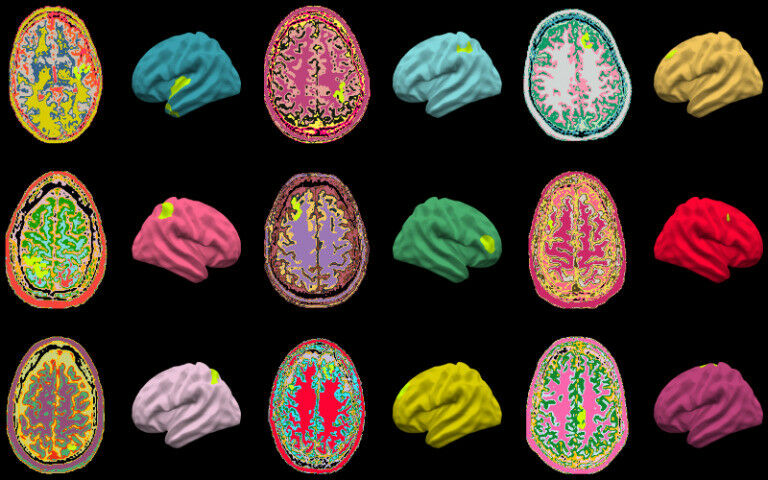

Brain abnormalities identified by the MELD AI algorithm (highlighted in lime green) on MRI scans of children and adults with epilepsy from around the world.

Brain abnormalities identified by the MELD AI algorithm (highlighted in lime green) on MRI scans of children and adults with epilepsy from around the world. An artificial intelligence (AI) algorithm that can detect subtle brain abnormalities which cause epileptic seizures has been developed by a UCL-led team of international researchers. The Multicentre Epilepsy Lesion Detection project (MELD) used over 1,000 patient MRI scans from 22 global epilepsy centres to develop the algorithm, which provides reports of where abnormalities are in cases of drug-resistant focal cortical dysplasia (FCD) - a leading cause of epilepsy. FCDs are areas of the brain that have developed abnormally and often cause drug-resistant epilepsy. It is typically treated with surgery, however identifying the lesions from an MRI is an ongoing challenge for clinicians, as MRI scans in FCDs can look normal. To develop the algorithm, the team quantified cortical features from the MRI scans, such as how thick or folded the cortex/brain surface was, and used around 300,000 locations across the brain. Researchers then trained the algorithm on examples labelled by expert radiologists as either being a healthy brain or having FCD - dependant on their patterns and features.